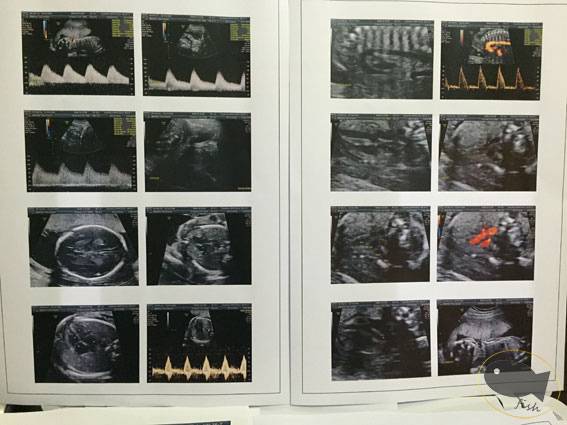

從頭到尾看的項目包括:

- 頭:頭圍、大腦、小腦、頭骨...等

- 五官:眼、耳、鼻、鼻孔、鼻骨、嘴唇、耳朵..等

- 胸腔:胸、肺、心臟(心房/心室)、心跳、心臟血液流動...等

- 腹部:胃、肝、腎、橫膈膜、膀胱、生殖器、臍帶...等

- 四肢:手、手掌、手指頭、手臂骨骼長度、腳、腳掌、腳趾頭、大腿小腿骨骼長度...等

- 血液:各處動脈、靜脈血液流動...等

- 其他:子宮頸長度、胎盤、羊水...等

會附上所有檢查項目的數據跟確認表,

報告裡也會附上剛剛拍攝的所有相片,

洋洋灑灑的總共10張A4報告,並有將近50張相片,